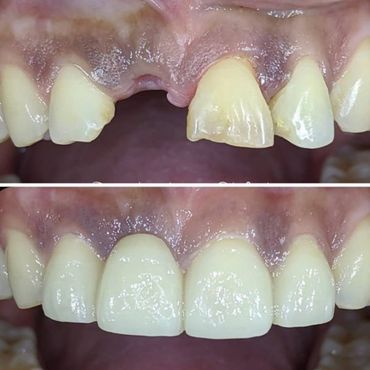

When natural teeth are lost, the face begins to show signs of aging due to bone loss. If you wait too long, the food chewing muscles begin to shorten to accommodate the reduced space between your nose and your chin. Missing one or more teeth could affect the overall health of the surrounding teeth and gums. A dental Implant is the solution to stop bone loss and restore the facial skeletal structure.

A dental implant is an artificial replacement of the root of a tooth. It is a viable option for people of all ages who are in good oral health. The implant is normally a cylinder-shaped metal post inserted and fused into the bone. A replacement tooth is then fitted onto it once it fuses into the bone. With the implant, one can eat, chew, and brush normally.

With proper care, dental implants will last a lifetime.